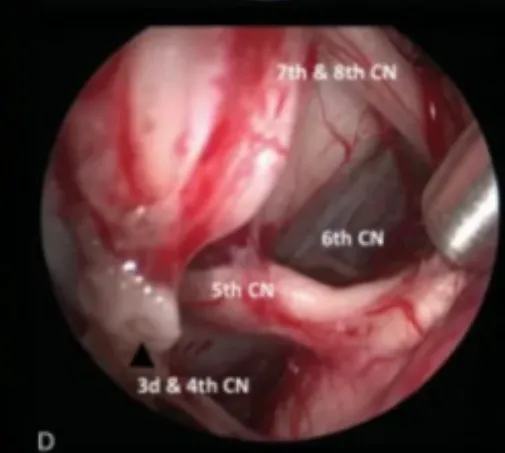

图2术中图像:(A)在经后岩骨入路时,横窦-乙状窦连接处的后部移位,为颞叶与后颅窝之间的手术通道(白色箭头)。

(B)脚间池蛛网膜的初步解剖分离,肿瘤的暴露。

(C)内镜辅助可以对手术床进行详细检查。

(D)探查周围的神经血管解剖结构

注:CN,颅神经;L视神经N,左视神经;R视神经N,右视神经。

在此手术视频中讨论并说明了后岩骨入路有关的技术和详细的术中要点,包括横窦-乙状窦连接的后部移位,在天幕切开时如何保护静脉结构,肿瘤切除时第三脑室底部的辨认和保护,细致的多层次闭合等。